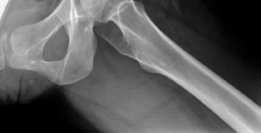

Standard preoperative imaging must include an anteroposterior (AP) pelvis, cross-table lateral, and false-profile view of the affected hip. These evaluate for dysplasia, impingement morphology (cam/pincer), and degenerative changes.

Magnetic Resonance Arthrography (MRA) is the gold standard for evaluating the capsuloligamentous complex. Extravasation of contrast anteriorly often delineates the size and location of the capsular defect. MRA also assesses labral integrity, chondral damage, and the viability of the femoral head. A 3D computed tomography (CT) scan is highly recommended to quantify femoral anteversion and acetabular version, as unrecognized osseous malorientation (e.g., severe femoral retroversion) will predispose the reconstruction to failure if not addressed concurrently with a derotational osteotomy.